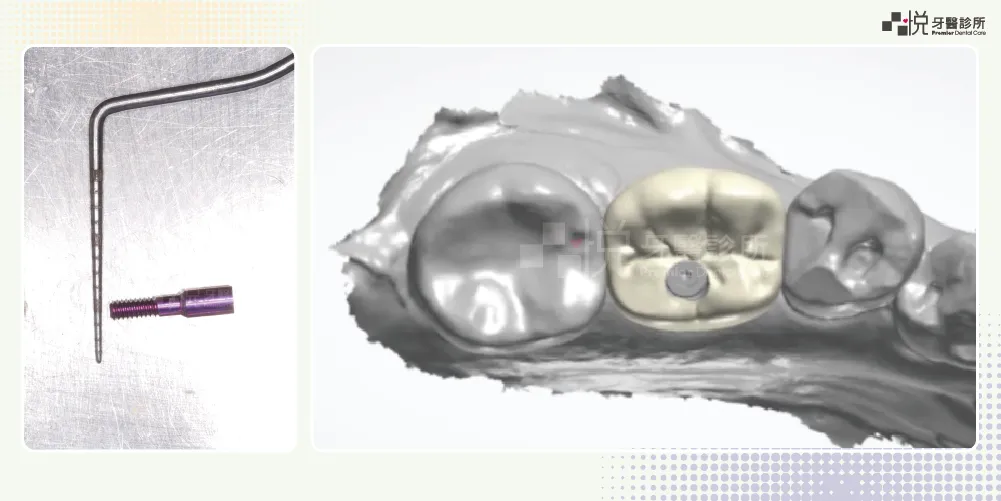

因為植體中心的螺絲很細,為了增加植牙假牙的壽命,在咬力大或是會磨牙的病患身上,會特別把假牙的咬合面設計的較平坦、面積較小,研究顯示可大幅增加假牙壽命,但是可能會覺得咬合力道稍差。